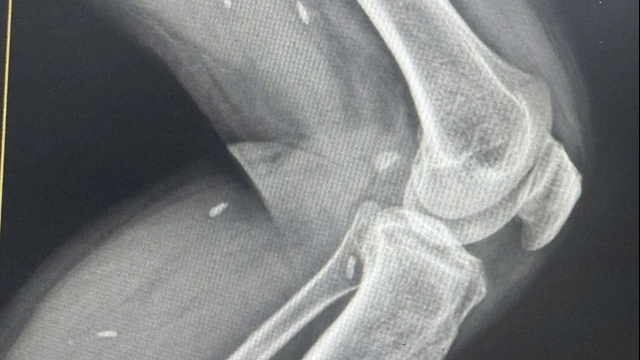

Theo bác sĩ Dũng, tình trạng trẻ khi nhập viện rất nguy kịch, da tím tái, xuất hiện các cơn ngừng thở, chỉ số oxy trong máu liên tục giảm, suy hô hấp nặng, phải thở máy. Bác sĩ chỉ định làm xét nghiệm chuyên sâu ngay tại giường. Kết quả trẻ nhiễm virus hợp bào hô hấp (RSV) gây viêm phổi nặng, xẹp toàn bộ phổi bên phải.

| Sau 10 ngày điều trị, trẻ qua nguy kịch, sức khỏe ổn định (Ảnh: BVCC) |

Sau 10 ngày điều trị, trẻ qua nguy kịch, sức khỏe ổn định.